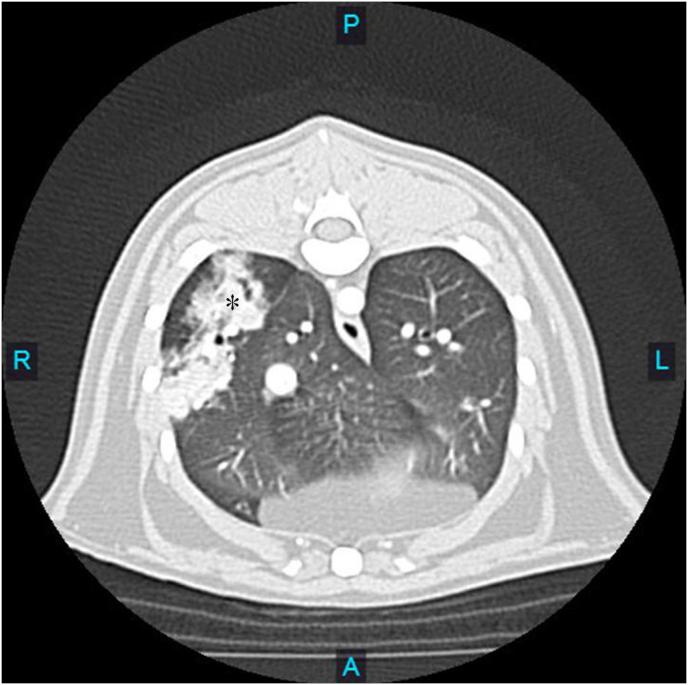

We hereby report a unique manifestation of feline cryptococcosis in the form of extensively consolidated lipoid pneumonia resulting in an isolated space-occupying lung lobe mass. Lung lobectomy was performed and a diagnosis of severe lipoid pneumonia with intra-lesional was made. The patient was asymptomatic for respiratory disease and no abnormalities of the upper respiratory tract were identified. Anti-fungal therapy was initiated following the diagnosis and the patient recovered without complication.

我们在此报告一例猫隐球菌病的独特表现,其形式为广泛实变的类脂性肺炎,导致孤立的肺叶占位性肿块。进行了肺叶切除术,并诊断为伴有病灶内[此处原文intra-lesional后内容缺失]的严重类脂性肺炎。该患者无呼吸道疾病症状,上呼吸道未发现异常。诊断后开始抗真菌治疗,患者康复且无并发症。